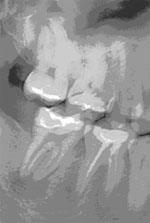

A gyökérkezelés célja a fertőzött szövetek eltávolítása a gyökércsatornából, belső tisztítás és a megfelelő hosszúságú és méretű üreg megformálása. Az így előkészített helyre a gyökértömő anyag behelyezhető, mely inertté teszi a fogat. Az érzéstelenítés után a kemény foganyagot átfúrva nyílást ejtünk az idegszál tetején a fogban, majd megfelelő méretű hozzáférést biztosítunk a gépi gyökérkezelő eszközök számára. A gyökércsatorna hosszának meghatározására elektromos hosszmeghatározási módszert alkalmazunk, bizonytalan esetben tűkontroll-felvételt készítünk. Az általunk használt gépi gyökérkezelő eszközök sokkal kónikusabbak, mint a hagyományos kézi eszközök, ezáltal nagyobb hatásfokú a tisztítás és nagyszámú beteganyagon értünk el hosszútávú sikereket. A csatornát vegyszerrel is átöblítjük, ami szintén a csírátlanítást szolgálja. Megfelelő méret elérése után paszta állagú és szilárd gyökértömő anyagot helyezünk a csatornákba, majd a fogat ideiglenes tömőanyaggal látjuk el a koronai részén.

Sajnos a már korábban gyökértömött fogak is fájhatnak (pl. helytelen munkahossz választás esetén, elnézett és nem kezelt csatorna, de lehet anatómiai akadály miatt is, mondjuk, ha a fő csatorna kettéágazik, stb.). Ez sok esetben a fog újra kigyökérkezelésével, a gyökértömés revíziójával helyrehozható. Ilyenkor a régi gyökértömés eltávolítása nehézkes lehet.